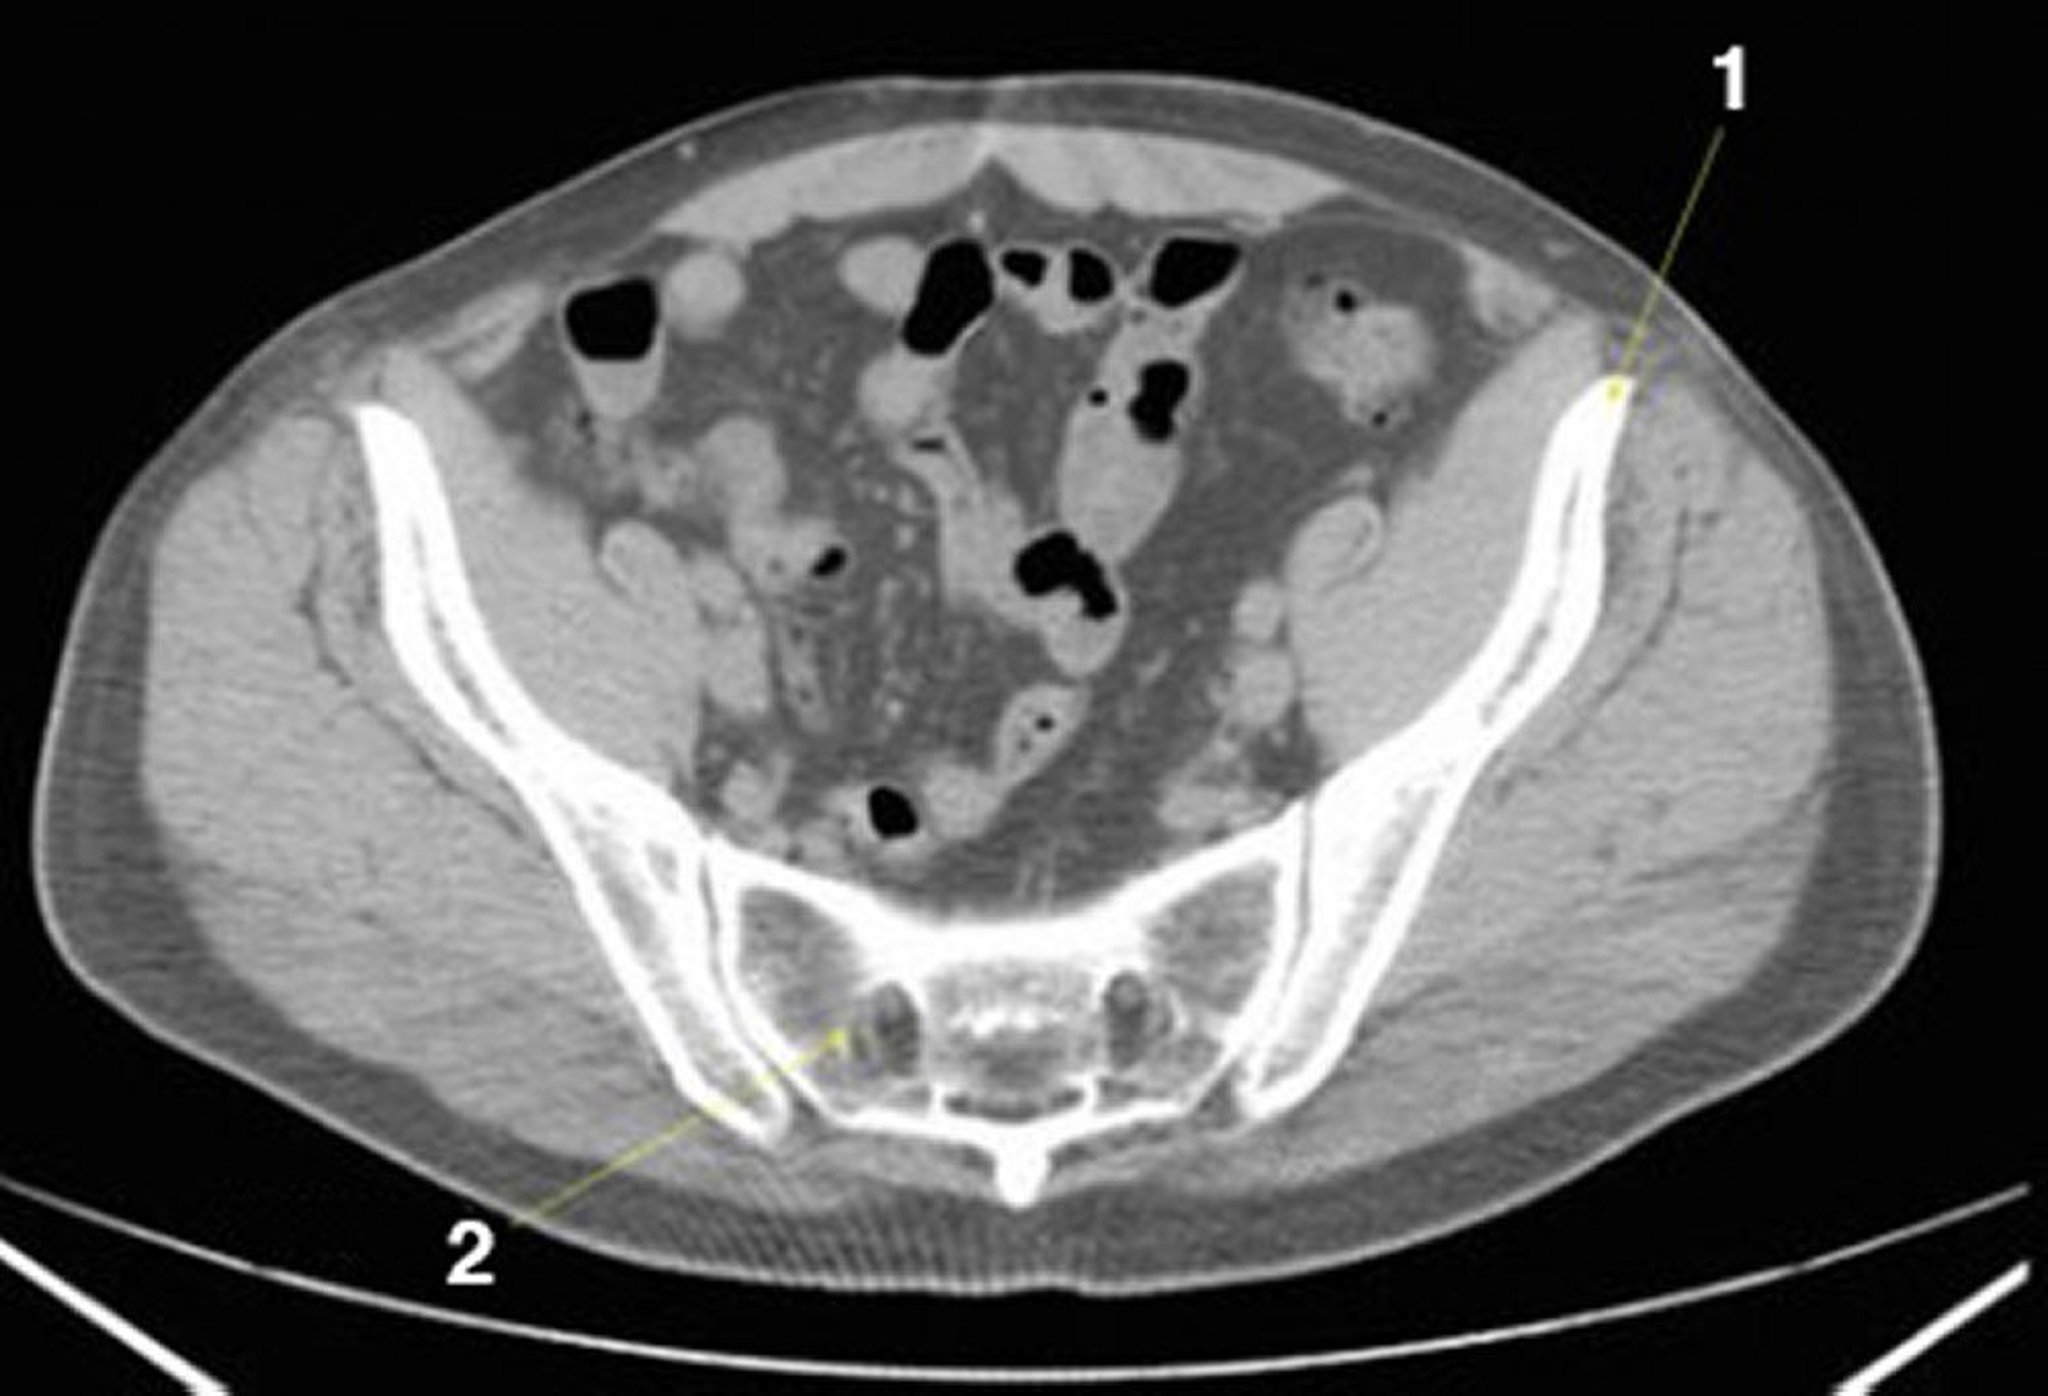

Phim chụp CT vùng bụng và vùng chậu không thuốc cản quang cho thấy giải phẫu bình thường (lát cắt 23)

1 = vùng chậu; 2 = xương cụt.